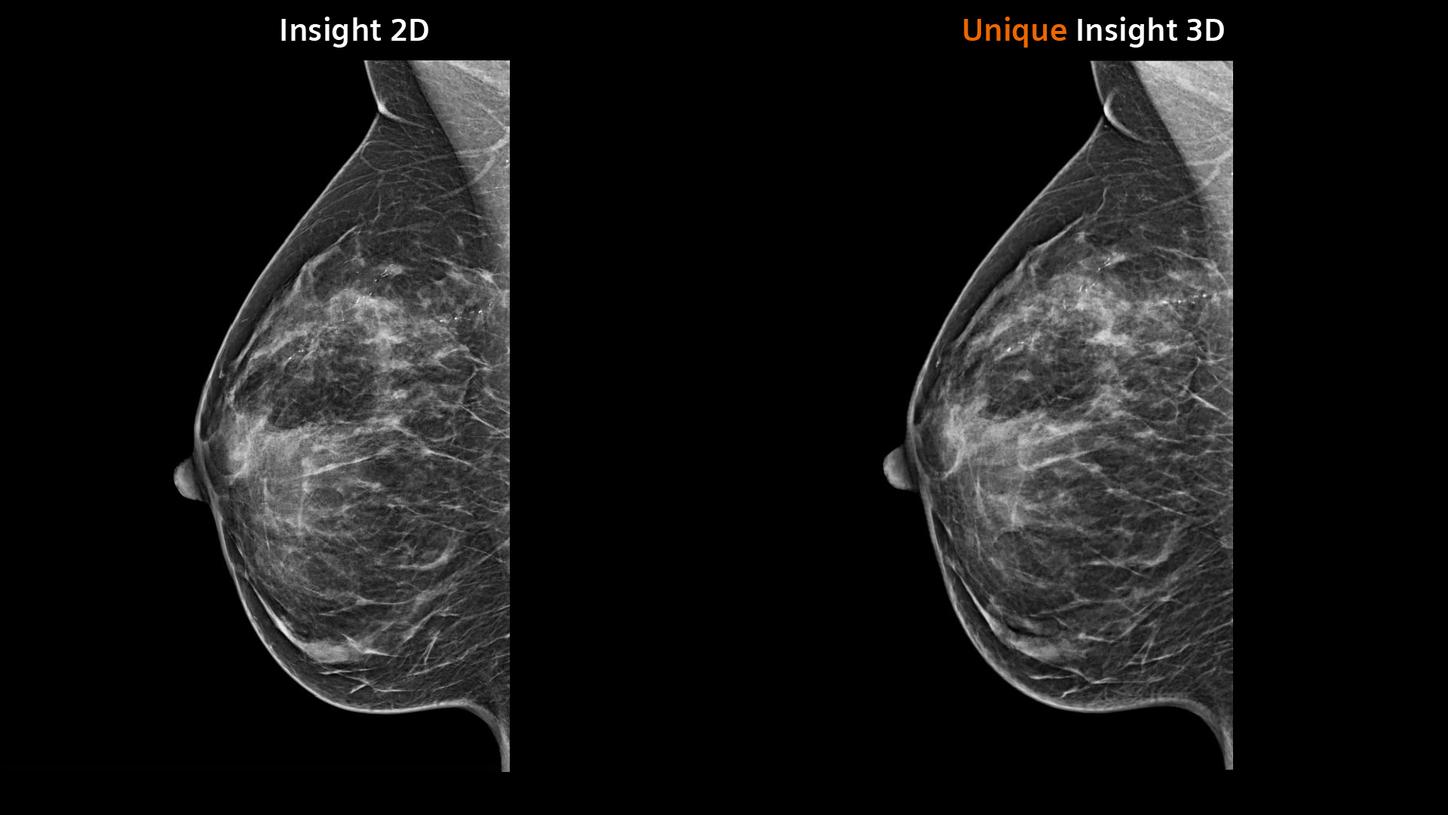

Synthesized 2D mammographic imaging (Insight 2D) and unique, rotating synthesized

3D mammographic imaging (Insight 3D)Examination duration